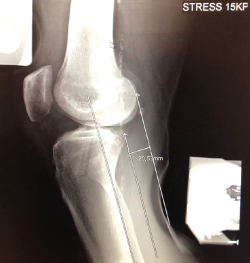

Figura 1. Laxitud en el cajón anterior. Radiología forzada.

Desde el punto de vista clínico, se consideran motivo de revisión quirúrgica aquellos casos en los que exista un desplazamiento anterior comparado con el contralateral mayor de 5 mm, pivot shift de alto grado, dolor, inflamación, sensación subjetiva de inestabilidad y limitación funcional para las actividades de la vida diaria o deportiva(9,10). Algunos autores han rebajado esta cifra a 3 mm con respecto a la rodilla contralateral o 10 mm de desplazamiento absoluto en el plano sagital(11)(Figura 1).